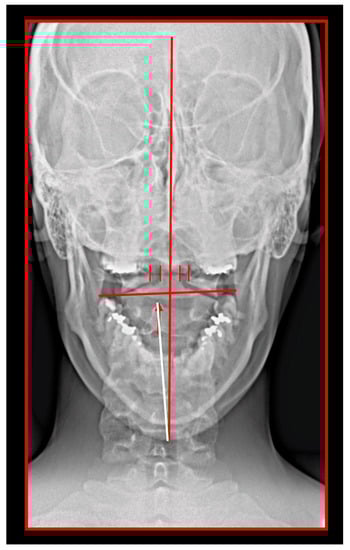

The Importance of the Skeletal Midline

11.5. Axis and Atlas Derotation